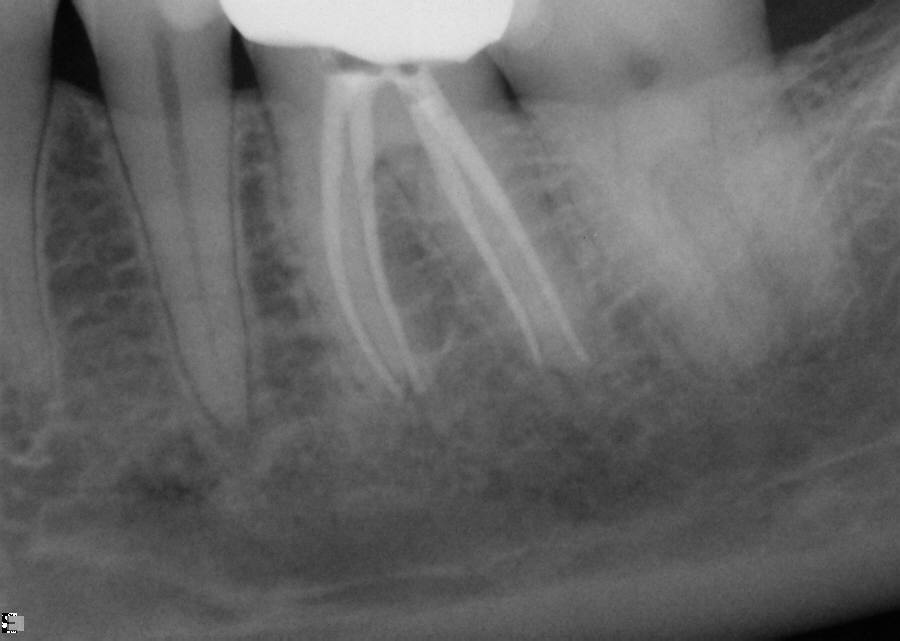

Fig 12. Working PA depicting arduous mesial bends and two mesial canals.

Figure 12